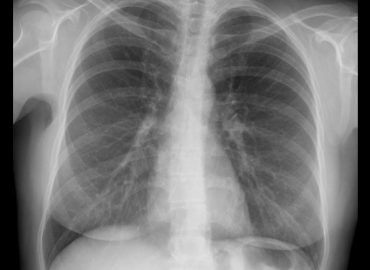

MC: Broncoespasmos.